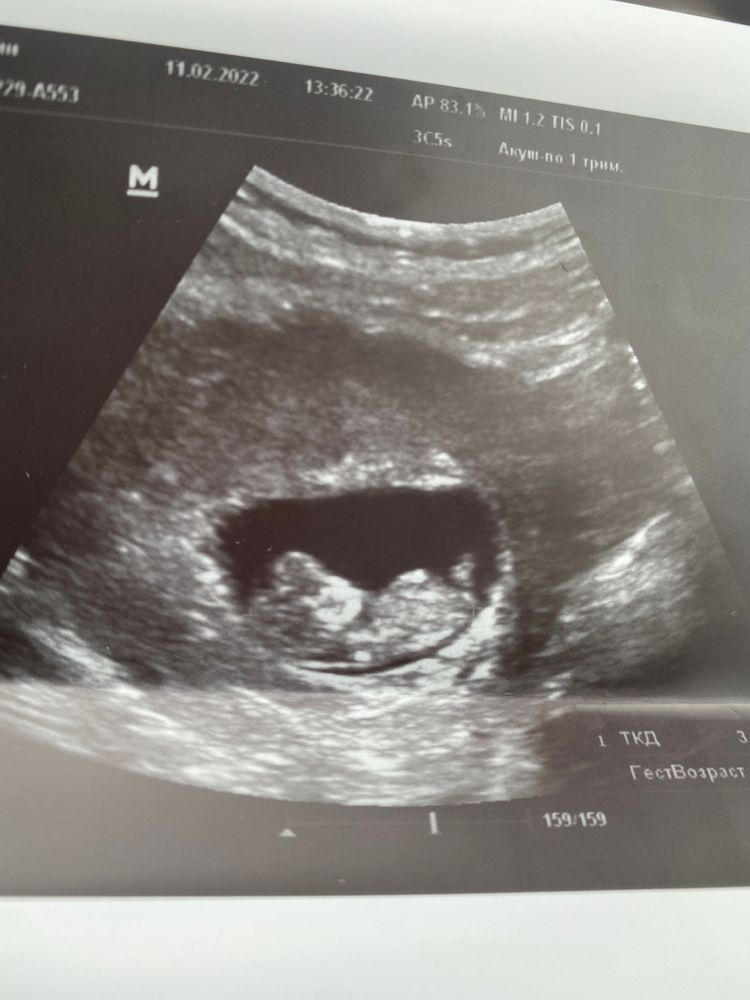

Узи 10+3 недель, ведь рано для определения пола

На таком сроке половой бугорок есть и у мальчиков, и у девочек, а все зависит от уголка наклона. Мне в 12+2 сказали пол (но я делала нипт до этого и врач не ошиблась), но смотрели еще в 3д.

У меня в 11,1 был в малыша прям девчачий половой бугорок, а когда снизу врач смотрела, то сказала, что пока ничего не торчит. На скрининге в 12,1 уже половой бугорок торчал вверх, и в 15 недель врач по узи сказала, что мальчик, но я знала, что у меня мальчик, потому что в 9,5 недель кровь сдавала на определение пола. Поэтому я бы на таком сроке на узи пока ну совсем не ориентировалась бы.

На 1 скрининге однозначно могут увидеть, в 10 недель не уверена, что могут определить...